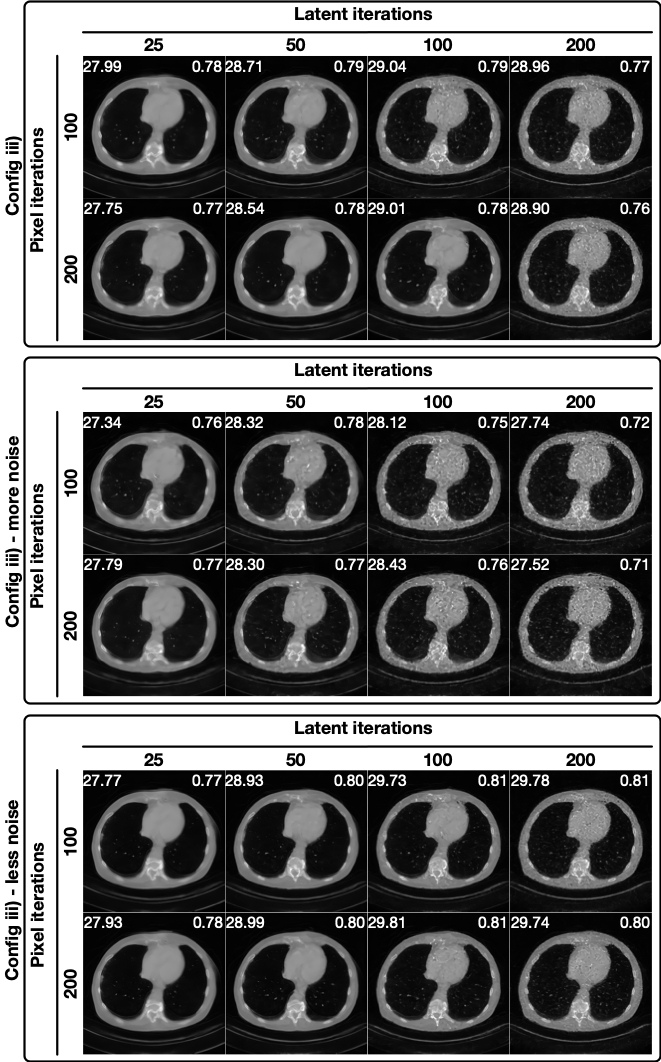

Data Consistency for Latent Diffusion: Gradient or Optimization? In latent diffusion models, enforcing data consistency via gradients is more challenging than in pixel-space diffusion (Fabian et al., 2024), as the gradients must propagate through the VQ-VAE decoder. As shown in Figure 5, PSLD (a representative latent diffusion method that relies solely on data consistency gradients) produces discontinuities in the reconstruction, even under noise-free conditions (i.e., 40 projections without noise). Similar artifacts appear frequently across configurations (see Figure 2), indicating a structural limitation of gradient-based enforcement in latent space.

In contrast, methods that incorporate explicit data consistency optimization steps, such as ReSample, can effectively correct these discontinuities and produce more coherent reconstructions in noise-free settings. However, as illustrated in Figure 5, aggressively enforcing data consistency through optimization steps can become detrimental in the presence of measurement noise (e.g., 80 projections with noise). In such cases, the reconstruction may overfit to noisy measurements, leading to degraded image quality and the amplification of noise-like features.